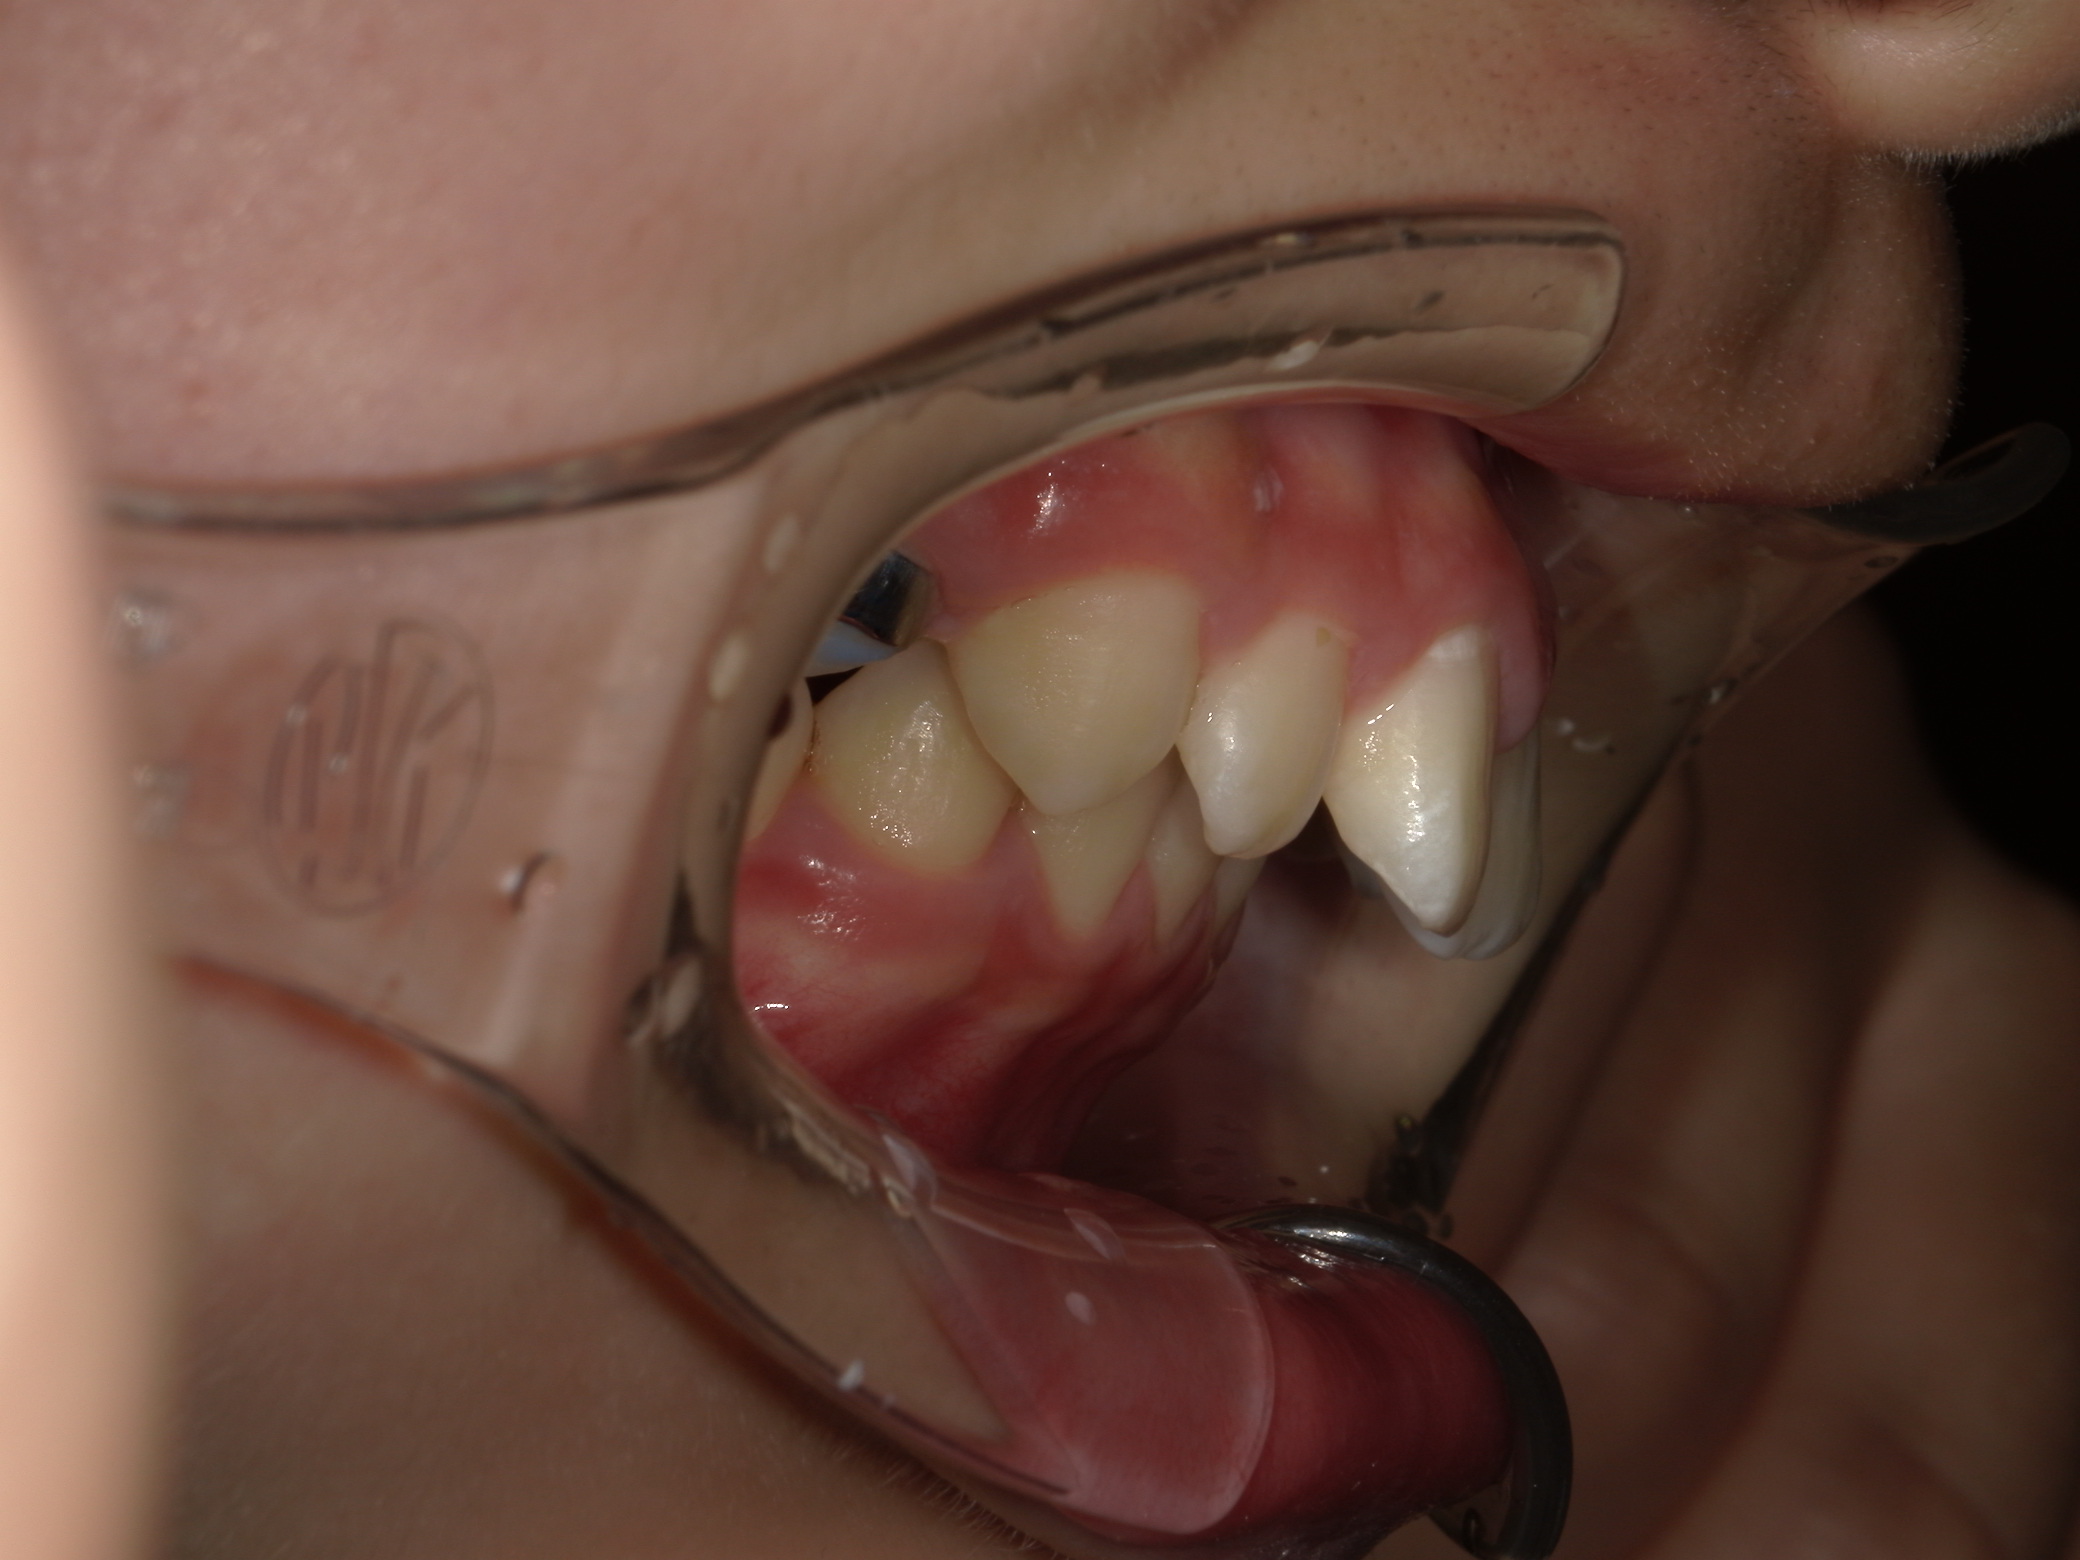

術前

装着後

術後

上の前歯の突出感が気になる子はぜひご相談ください♪